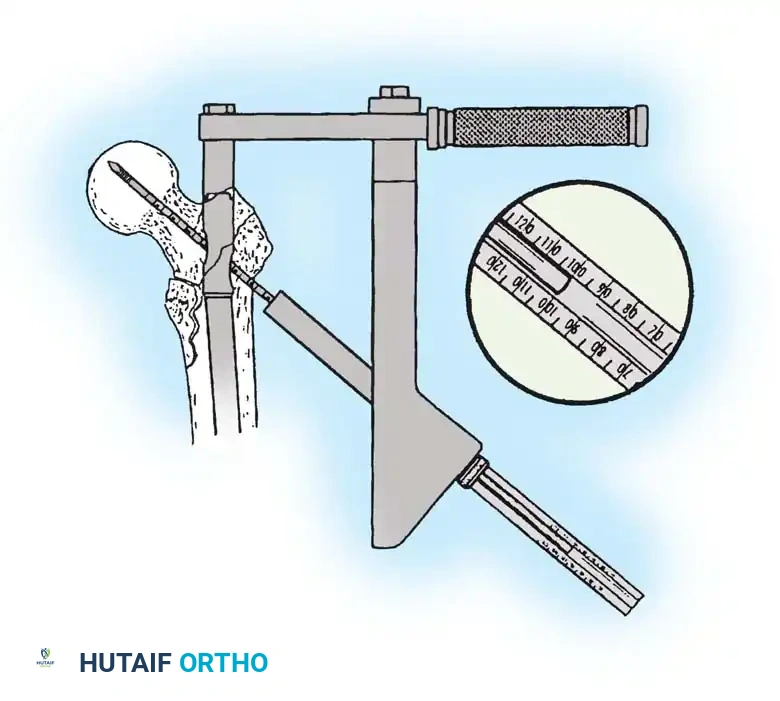

The Tip-Apex Distance (TAD):

Described by Baumgaertner, the TAD is the sum of the distance from the tip of the lag screw to the apex of the femoral head on both the AP and lateral radiographs. A TAD of less than 25 mm is strongly predictive of successful fixation; a TAD > 25 mm significantly increases the risk of screw cut-out.

4. Reaming and Lag Screw Insertion

Once the guide wire is perfectly positioned, the lateral cortex is opened, and the femoral neck is reamed over the wire.

Reaming of the femoral neck and head over the precisely placed guide wire, preparing the channel for the lag screw.

The lag screw is then inserted. It is crucial not to over-insert the screw, which can penetrate the articular cartilage, nor to under-insert it, which compromises fixation.